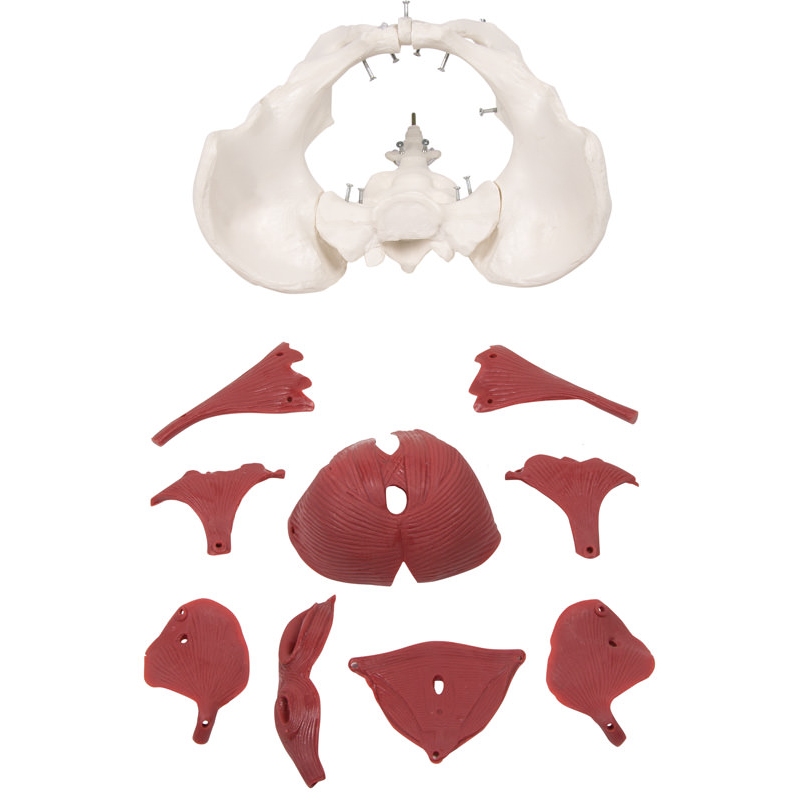

Model ženskega medeničnega dna, 12 delov

Ta novi model ženske medenice z muskulaturo medeničnega dna predstavlja medenično dno v svojih plasteh. Predstavljene so naslednje mišice, ki jih je mogoče odstraniti:

- Obturatorius internus mišica (levo in desno)

- Piriformis mišica (levo in desno)

- Coccygeus mišica ( levo in desno)

- Medenična diafragma (mišica levator ani, sestavljena iz mišice puborectalis, mišice pubococcygeus in mišice iliococcygeus)

- Urogenitalna diafragma (sestavljena iz globoke prečne mišice presredka, površinske prečne mišice presredka in mišice ischiocavernosus)

- Sfinkterji urogenitalni in prebavni trakt (sestavljen iz zunanjega analnega sfinktra, sečnice in mišice bulbospongiozne)

Skupaj z dvema kolčnima kostema in križnico je model sestavljen iz skupno 12 delov. Mišice so pritrjene z zatiči, kar omogoča njihovo odstranitev za prikaz plasti. Ta model je popoln za tečaje gimnastike medeničnega dna, za tečaje priprave na porod, za izobraževanje babic ali preprosto za anatomske študije medeničnega dna.

Velikost: 27 x 18 x 17 cm

Teža: 1 kg